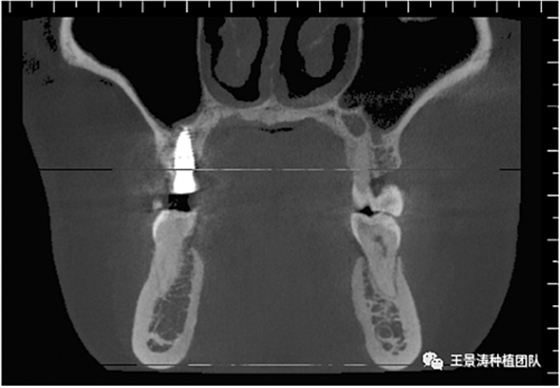

左側(cè)下頜第二磨牙及右側(cè)下頜第一磨牙同時即刻種植病例?;颊吣贻p女性,無系統(tǒng)性疾病。37及46殘冠及殘根,且46劈裂,無法冠修復,必須拔除。37根尖慢性炎癥,大量肉芽組織存在,46根分叉較高,根分叉骨質(zhì)尚可。CBCT示:根尖骨質(zhì)至下牙槽神經(jīng)管距離可滿足種植體的初期穩(wěn)定性,遂考慮即刻種植,并在種植體周邊填入骨粉并覆蓋骨膜,雙側(cè)的種植體初期穩(wěn)定性相差無幾,但考慮到37根尖慢性炎癥較大,遂給予埋入式種植。